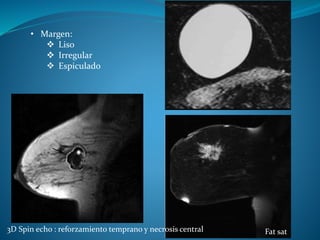

• Margen:

 Liso

 Irregular

 Espiculado

3D Spin echo : reforzamiento temprano y necrosis central Fat sat

• Margen:  Liso Irregular  Espiculado 3D Spin echo : reforzamiento temprano y necrosis central Fat sat